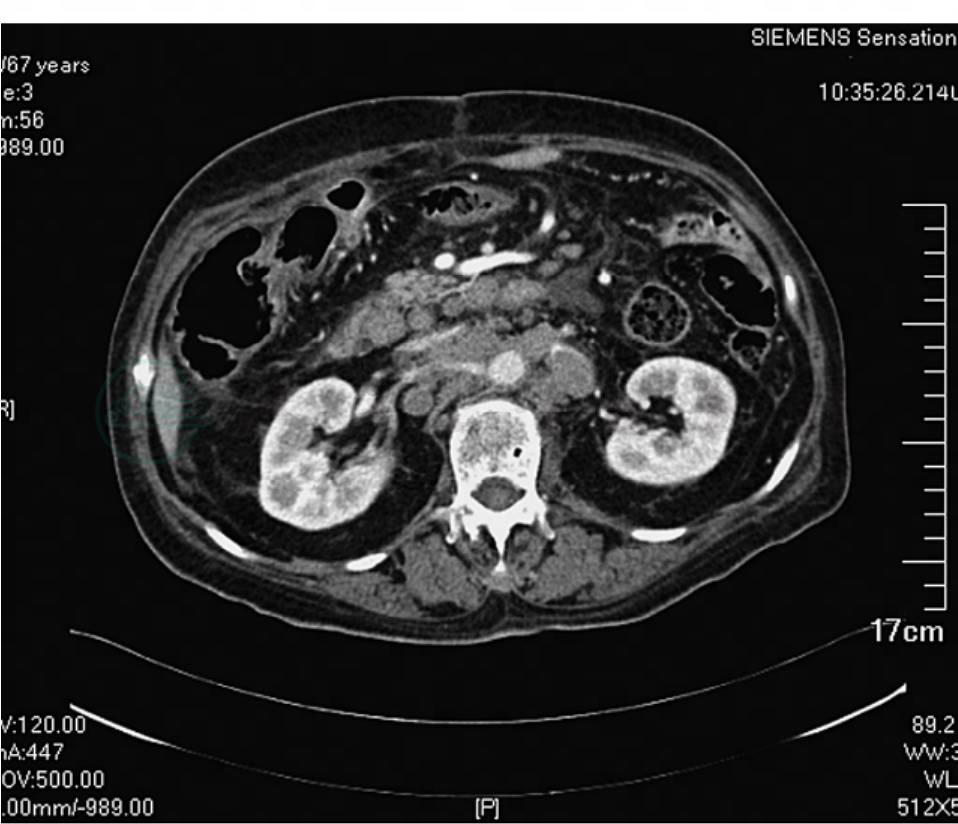

2.患者入院后完善血常规、血生化、凝血功能、便常规及肿瘤标志物等相关术前检查均未见明显异常。行全腹增强CT检查回报:胃窦部后下壁病变并表面溃疡,考虑胃癌可能性大,腹膜后淋巴结肿大,考虑转移(图4~图7)。

图4 术前CT提示胃窦溃疡性病变,腹膜后淋巴结肿大(一)

图5 术前CT提示胃窦溃疡性病变,腹膜后淋巴结肿大(二)

图6 术前CT提示胃窦溃疡性病变,腹膜后淋巴结肿大(三)

图7 术前CT提示胃窦溃疡性病变,腹膜后淋巴结肿大(四)